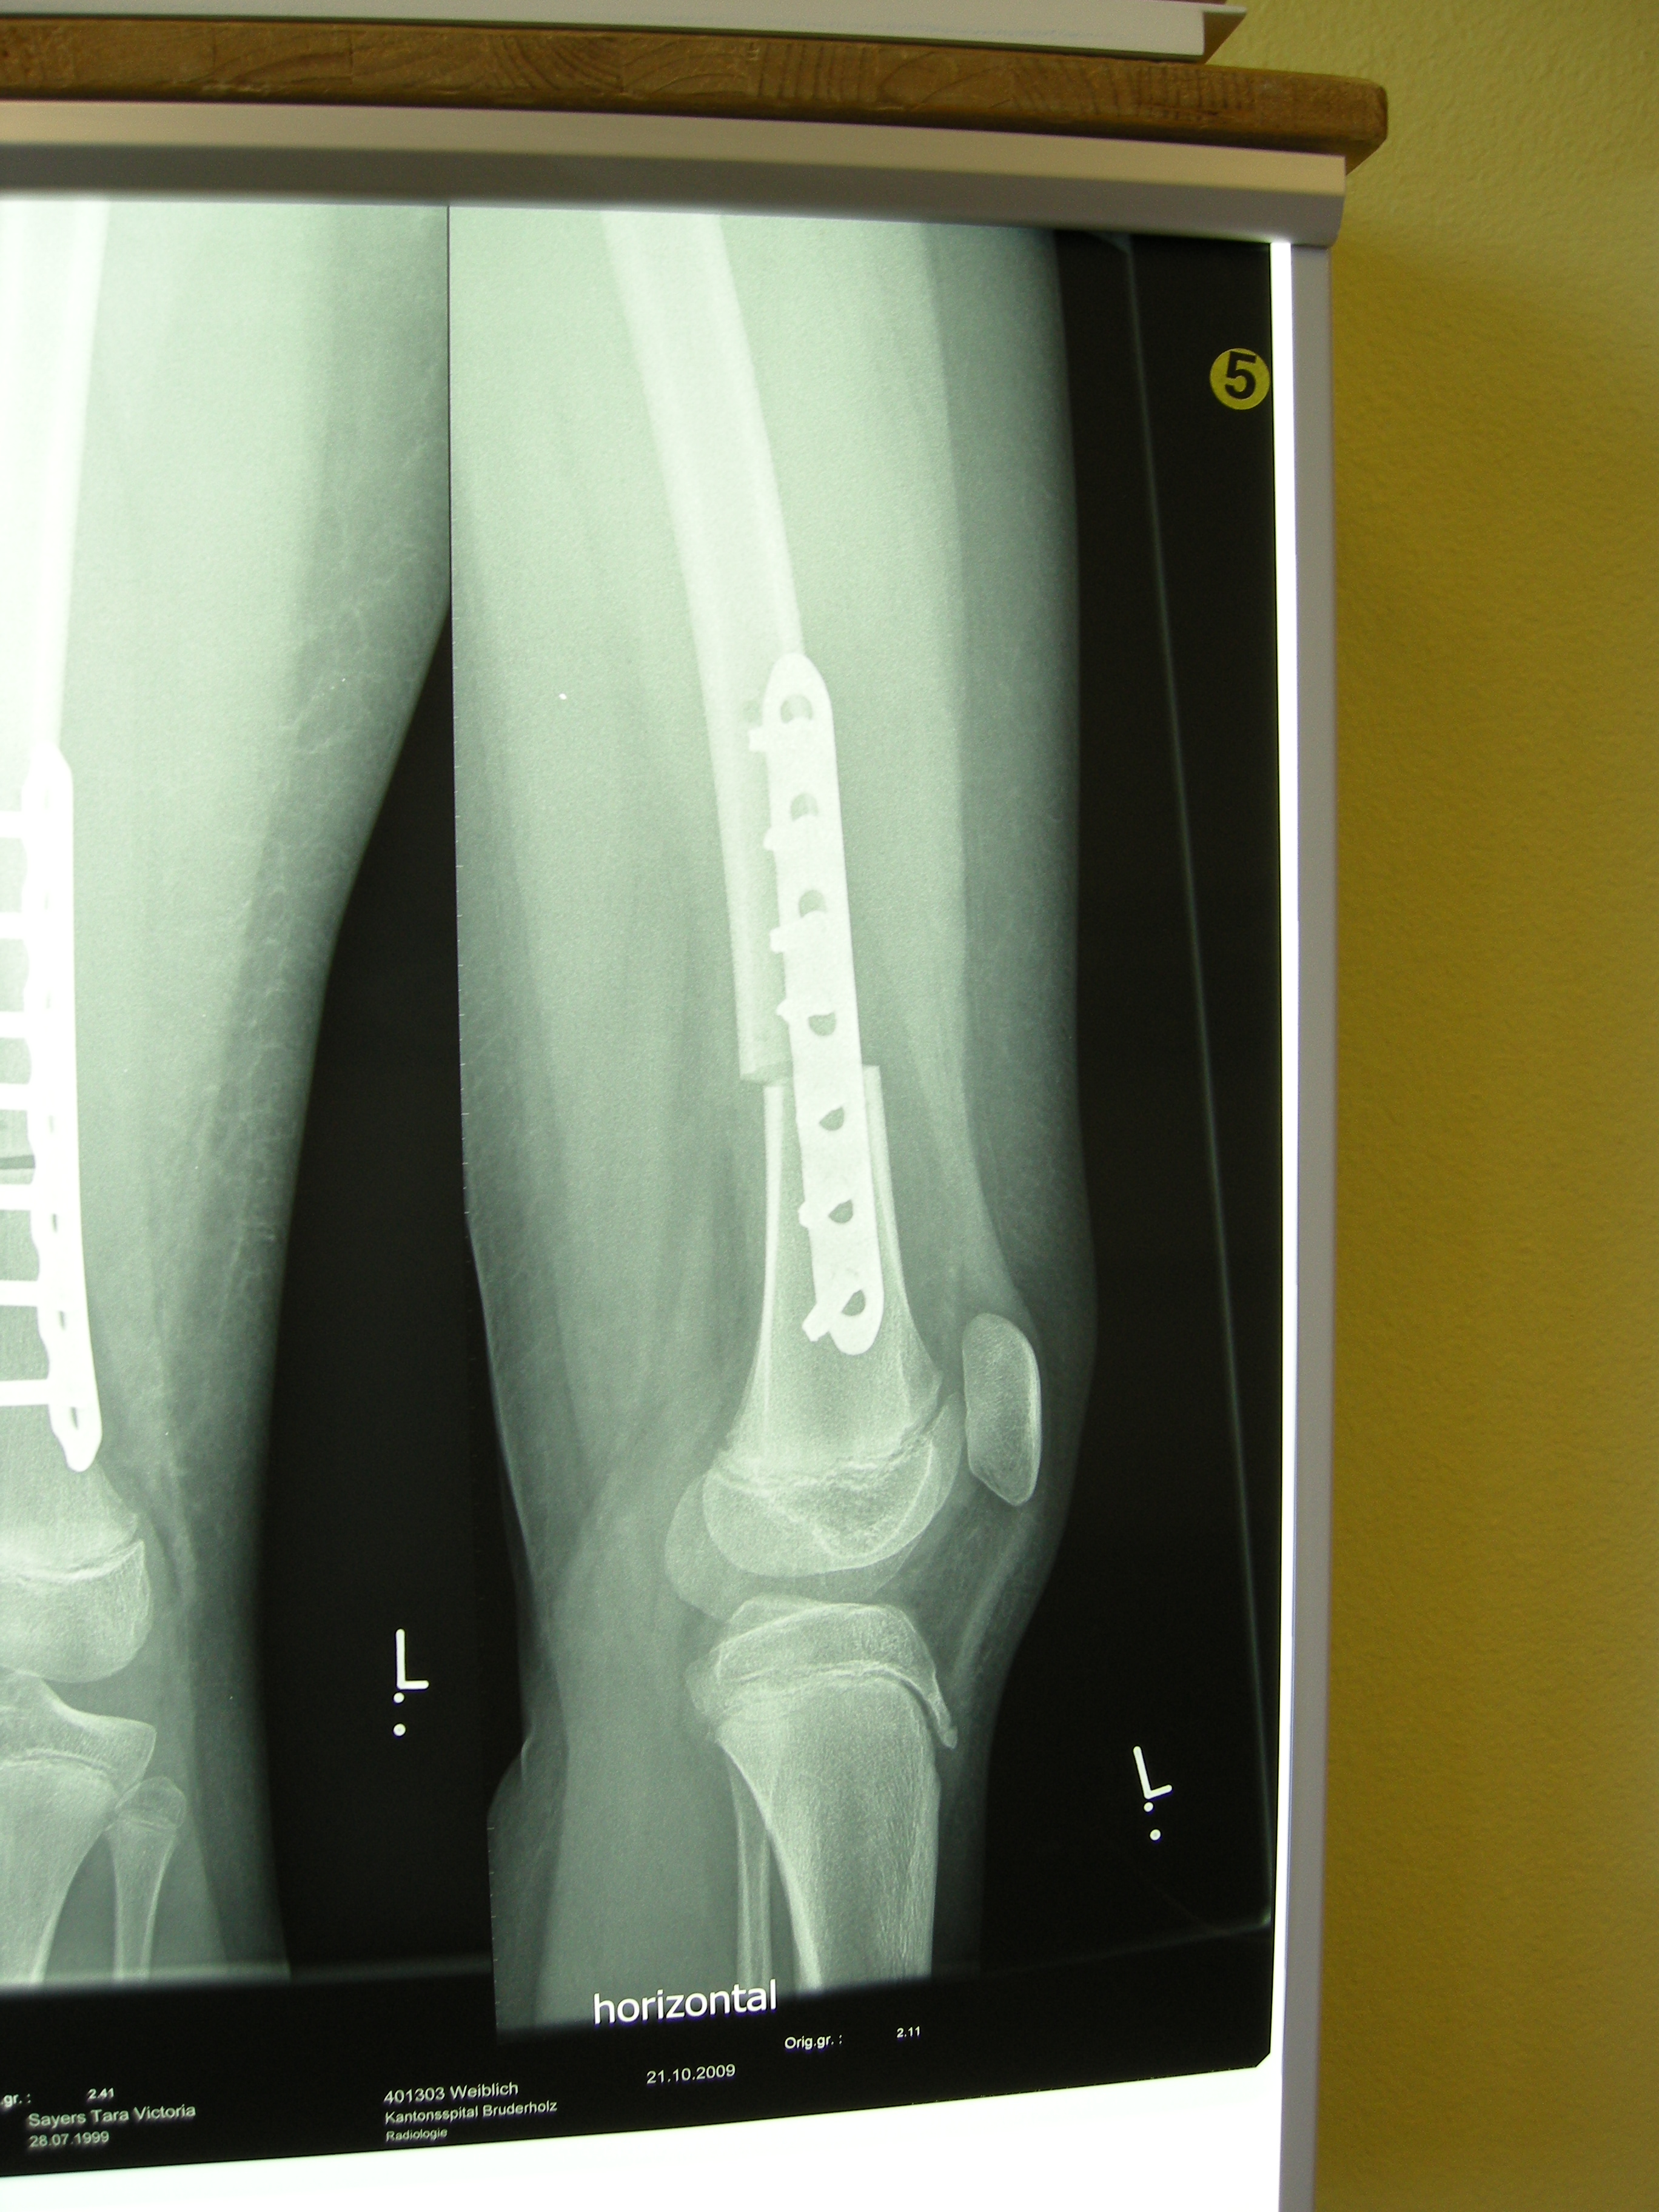

XRays